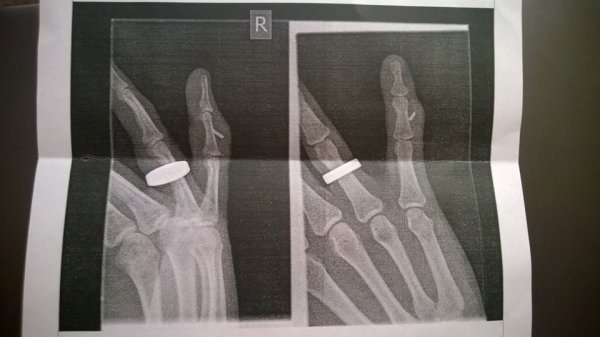

Выяснилось, что палец загноился, а металл застрял в противоположной от места вхождения части пальца. Достать два осколка получилось с помощью хирургического вмешательства, в общей сложности манипуляции заняли полтора часа. Теперь гомельчанину предстоит реабилитация.